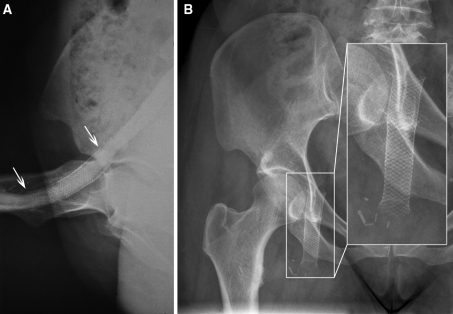

Stent integrity, with normal stent morphology, was documented in 14 of 15 cases (Fig. 1). One stent showed a single stent fracture (patient no. 14). We guess that the reason for this fracture was a calcified hematoma adjacent to the stent, which resulted in chronic mechanical stress (Fig. 2A–F). It is remarkable that even stents placed in the common femoral vein directly over the hip joint (patients no. 1 and 11 through 13) showed no fracture after 83 to 222 months later (Fig. 3A, B).

Fig. 3.

A X-ray of the right hip in a bent position after placement of two 12 × 75-mm Wallstents in the common femoral vein (patient no. 12) shows good adaption of the Wallstent to the curving course of the common femoral vein, with no signs of kinking or damage to the stent The upper and lower edges of the stent are marked with arrows. B X-ray of the hip of the same patient 18.5 years after placement shows that the Wallstent remained intact